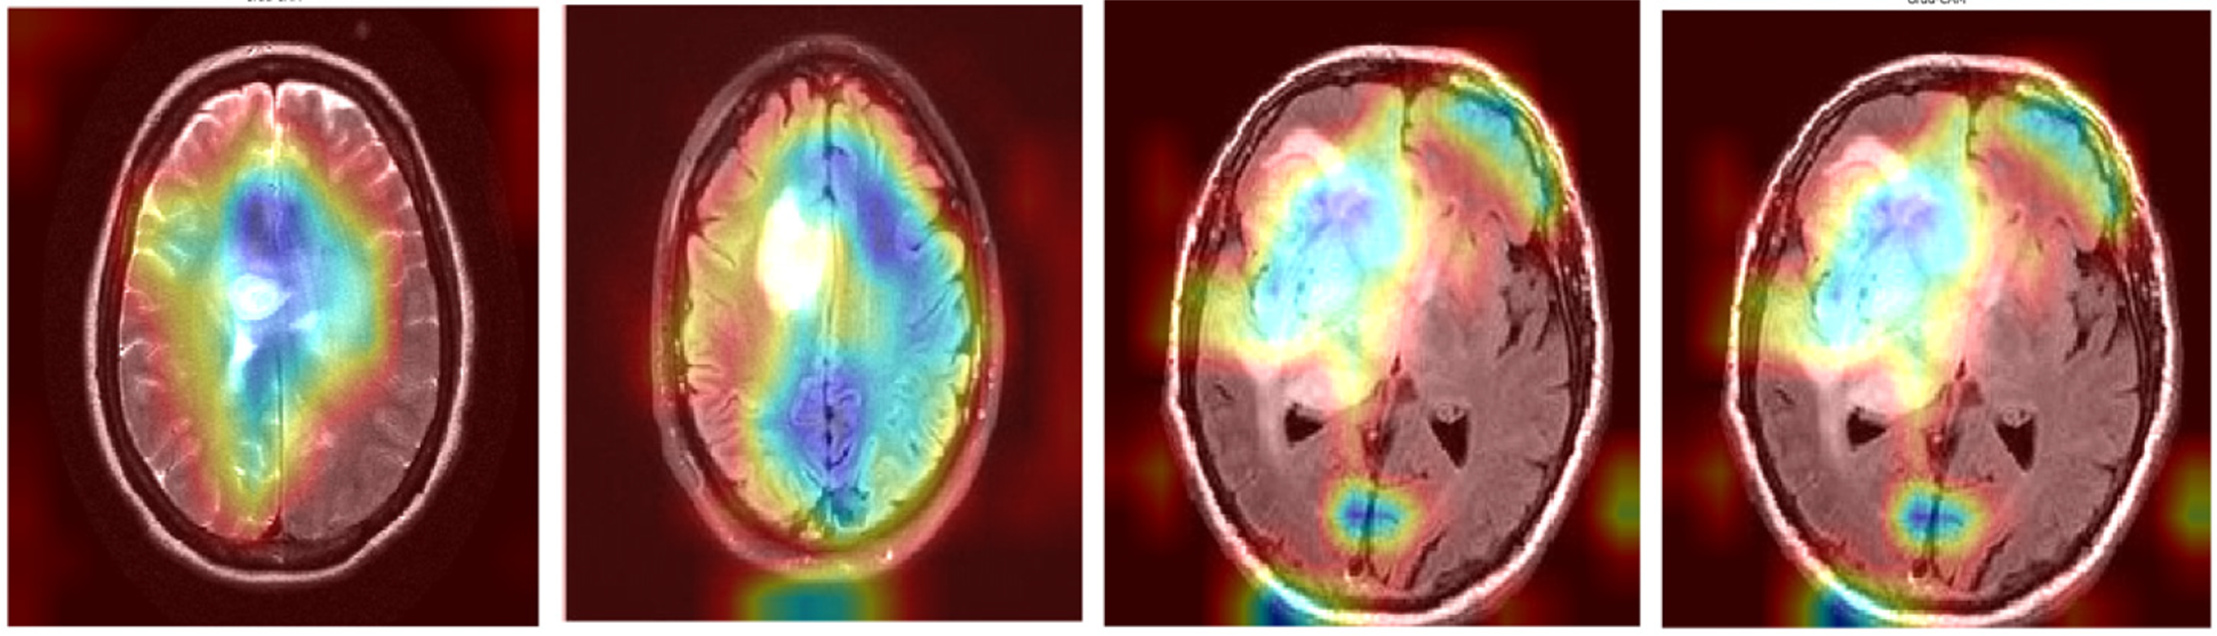

To visually demonstrate how the model processes and interprets MRI images, we present several Grad-CAM heatmaps, as shown in Fig. 6. A heatmap overlay on an MRI image, where the red-to-yellow gradient indicates areas of the highest importance, confirms that the tumor region is correctly identified. Fig. 7 illustrates the heatmaps generated by the basic CNN, the original DenseNet, and our modified DenseNet, highlighting the improved focus and clarity of our model. Fig. 8 shows a more detailed heatmap for MRI images, where tumors are not easily defined or are located in abnormal areas, illustrating how the model performs under stress.

Figure 6: Grad-CAM visualization on a typical tumor MRI

Figure 7: Comparison of grad-CAM heatmaps across different models